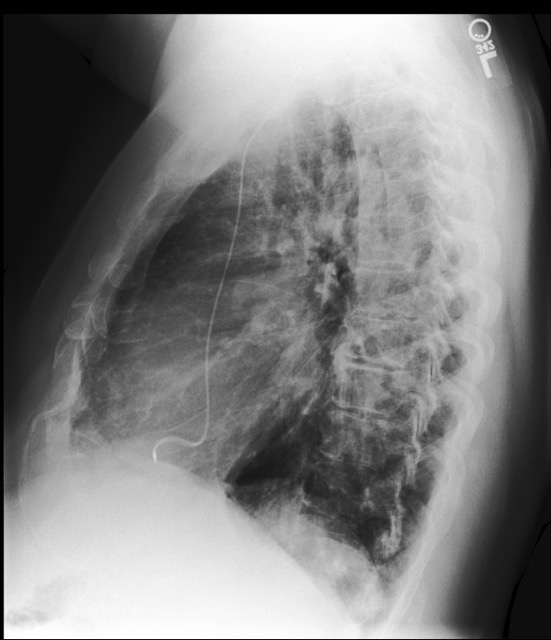

Refer to caption

Fig. 1: A patient can have multiple CXR studies over time. Each study can consist of multiple images, often representing different views of the chest. Note that the year of each study has been modified for anonymisation purposes.